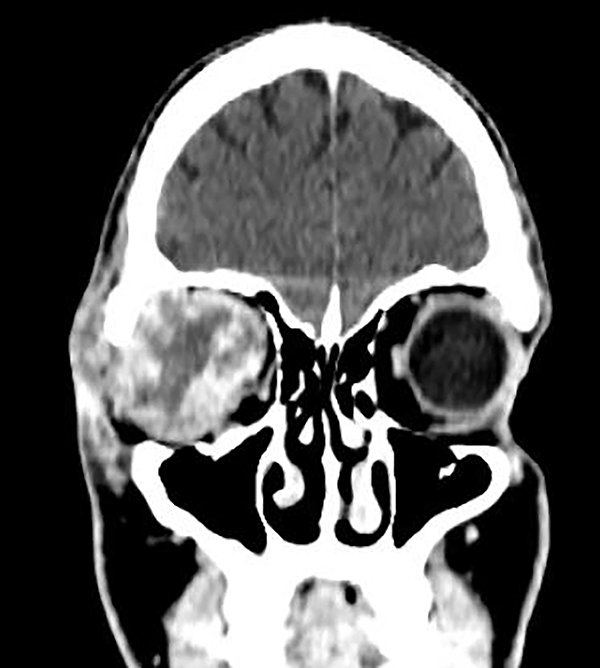

La tomografía computada (TC) de órbita derecha informó: formación heterogénea con efecto de masa sobre las estructuras adyacentes (musculares y nerviosas) de 40 mm asociada a proptosis del globo ocular homolateral (fig. 2).

Figura 2. TC de órbita: corte coronal con aumento de la densidad de partes blandas orbitarias derechas (músculos y nervios).